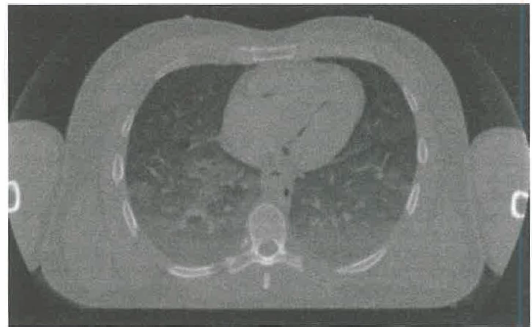

Gli artefatti possono compromettere la fedeltà diagnostica. I movimenti del paziente generano sfasamenti tra proiezioni con striature e aree ombreggiate nell’immagine ricostruita; contribuire possono anche indurimento di fascio, presenza di metalli, artefatti ad anello da rivelatori non perfettamente calibrati e errori di sincronizzazione. La stabilità operativa del tubo e dei rivelatori è quindi cruciale sia per l’ottimale ricostruzione sia per minimizzare gli artefatti di sistema. Un tipico apparato TC è mostrato in (Figura 07.28-09); esempi di immagini TC sono riportati in (Figura 07.28-10) e (Figura 07.28-11), dove, grazie all’acquisizione elicoidale e al raccordo dei piani, si ottiene la ricostruzione tridimensionale delle strutture anatomiche.

L’evoluzione dell’hardware di calcolo e delle interfacce ha reso possibile gestire grandi volumi di dati e flussi complessi, aprendo la strada a nuove metodiche d’imaging e a un’elaborazione avanzata delle immagini cliniche. Oltre a ecografia, microscopia digitale e digitalizzazione radiografica, un ruolo centrale è svolto dalle tecniche di tomografia, che ricostruiscono sezioni del corpo umano a partire da proiezioni acquisite da molteplici angolazioni. La ricostruzione tomografica mira a determinare la funzione f(x,y) che descrive le intensità (toni di grigio) in un piano specifico del soggetto (Figura 07.28-04). I piani di riferimento anatomici standard sono indicati in (Figura 07.28-05), con la possibilità di definire piani obliqui ove clinicamente necessario.